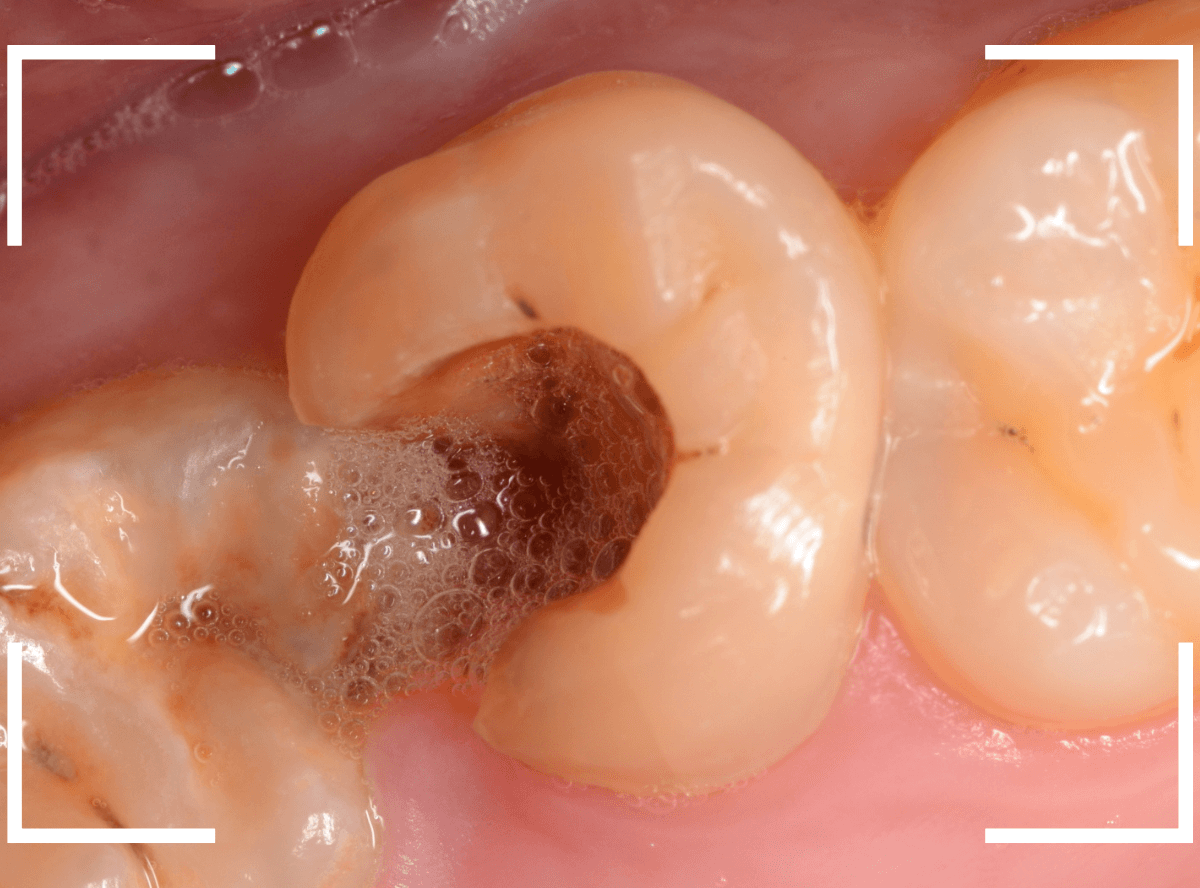

Case.4 見た目よりひどい虫歯になってしまっていたケース

今回は、痛みもなく、見た目にはまだ治療で何とかなりそうに見えるケースです。

大きな虫歯なのはわかりますが、治療で何とかなりそうにも見えます。

しかし、レントゲン写真で確認すると、実際には虫歯でボロボロで、歯の根っこだけの状態なのがわかります。

残念ながら抜歯が必要ですが、抜歯も難しくなる可能性が高いケースです。

予想通り、処置時に歯がバラバラになってしまい、時間がかかってしまいましたが、何とか抜歯を終わらせました。

虫歯の状態は見た目や症状だけではわかりません。

くれぐれも自己判断で放置することは避けてくださいね。